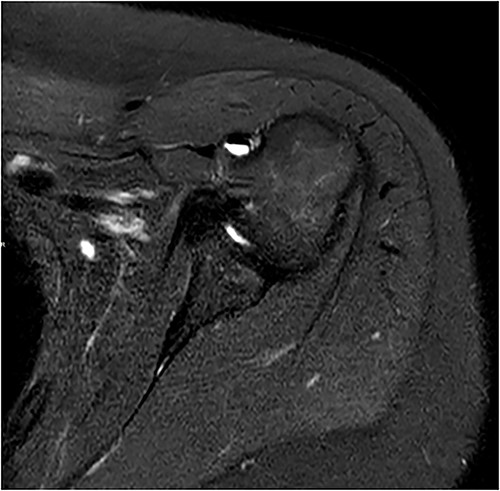

Standard anterior/posterior and lateral X-rays of the affected shoulder were done. The patient was diagnosed with adhesive capsulitis. She was therefore referred to office-based extensive rehabilitation program to improve range of motion and strengthen shoulder muscles. Though MRI does not play a rule in the diagnosis and management, we opted to do one, after consenting the patient, trying to understand the peculiarity of the case (Figs 1 and 2).

Coronal and axial T2 fat saturated image of left shoulder showing thickened inferior capsule of low T2 signal, characteristic of the freezing phase in adhesive capsulitis.